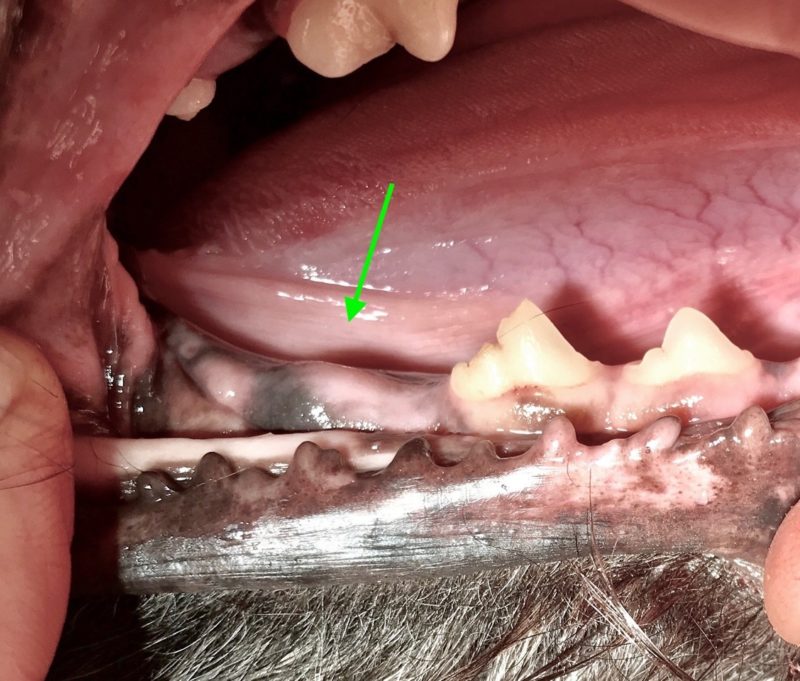

Der hübsche neun Jahre alte schwarze Mischlingsrüde Nando aus Italien wird vorgestellt, da die Besitzerin Zahnstein und einen unangenehmen Geruch aus der Maulhöhle festgestellt hat. Während der Untersuchung werden folgende Befunde erhoben: mittelgradiger Zahnstein an den meisten Zähnen, im Unter- und Oberkiefer je ein abgebrochener Schneidezahn (Abb. 1 und 2) und eine große „Zahnlücke“ im Unterkiefer rechts (Abb. 3). Hier scheinen die drei letzten Backenzähne zu fehlen. Nando ist ein sportlicher und schlanker Hund. Sein Herz schlägt regelmäßig und ohne Nebengeräusche. Dennoch untersuchen wir vor der Operation sein Blut, um mögliche Anästhesierisiken weitgehend ausschließen zu können. Wenige Tage später werden Nandos Zähne in Narkose sorgfältig von Zahnstein befreit und anschließend poliert. Von den beiden abgebrochenen Schneidezähnen und dem Bereich der vermeintlichen Zahnlücke im Unterkiefer werden Röntgenbilder angefertigt. Die Kronen der beiden Schneidezähne sind so tief abgebrochen, dass die Pulpahöhle offen liegt (Abb. 4). Im Bereich der „Zahnlücke“ zeigt das Röntgenbild Wurzelanteile nicht vollständig vorhandener oder vielleicht auch nicht vollständig ausgebildeter Zähne (Abb. 5).

Was bei augenscheinlicher Betrachtung zunächst wie eine ganz normale „Zahnlücke“ aussieht, stellt sich im Röntgenbild ganz anders dar. Bei Nando zeigt es an dieser Stelle Zahnreste, die kreuz und quer im Knochen des Unterkiefers liegen. Nun muss die Entscheidung gefällt werden, ob diese Zahnreste an Ort und Stelle belassen oder operativ entfernt werden. Wir haben die Zahnreste belassen, denn im Röntgenbild sind keine Hinweise auf eine Entzündung der Wurzelanteile oder des sie umgebenden Knochens oder die Ausbildung einer Zyste (s.u.) zu finden. Auch die äußerlich sichtbare Schleimhaut ist in diesem Bereich vollkommen reaktionslos. Nichts deutet auf die in der Tiefe des Unterkieferknochens liegenden Zahnanteile hin. Allerdings muss Nando in Zukunft weiter auf Entzündungs- oder Schmerzanzeichen überwacht werden, denn die Situation könnte sich im Verlaufe seines Lebens noch ändern. Mit zunehmendem Alter wird das jedoch immer unwahrscheinlicher. Eine regelmäßige Röntgenkontrolle zur Evaluierung der tiefliegenden Wurzelanteile ist wünschenswert.